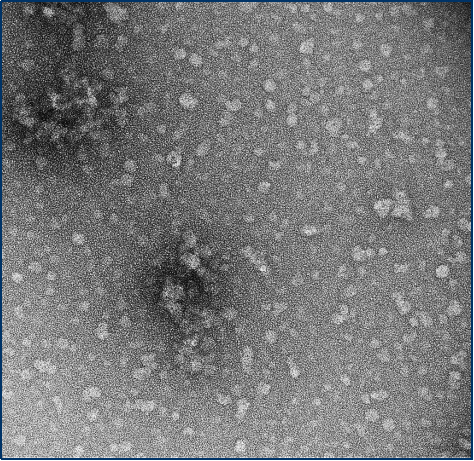

与不溶性原纤维相比,寡聚体是小的(25-30 nm)球状可溶结构。它们是与帕金森病相关的有毒聚集体,在结构上与原纤维不同。

负染色(铀酰酸)的电子显微镜图显示了Alpha 突触核蛋白的寡聚体结构,左侧为用多巴胺处理的alpha 突触核蛋白寡聚

来源:EM performed at U. of

British Columbia